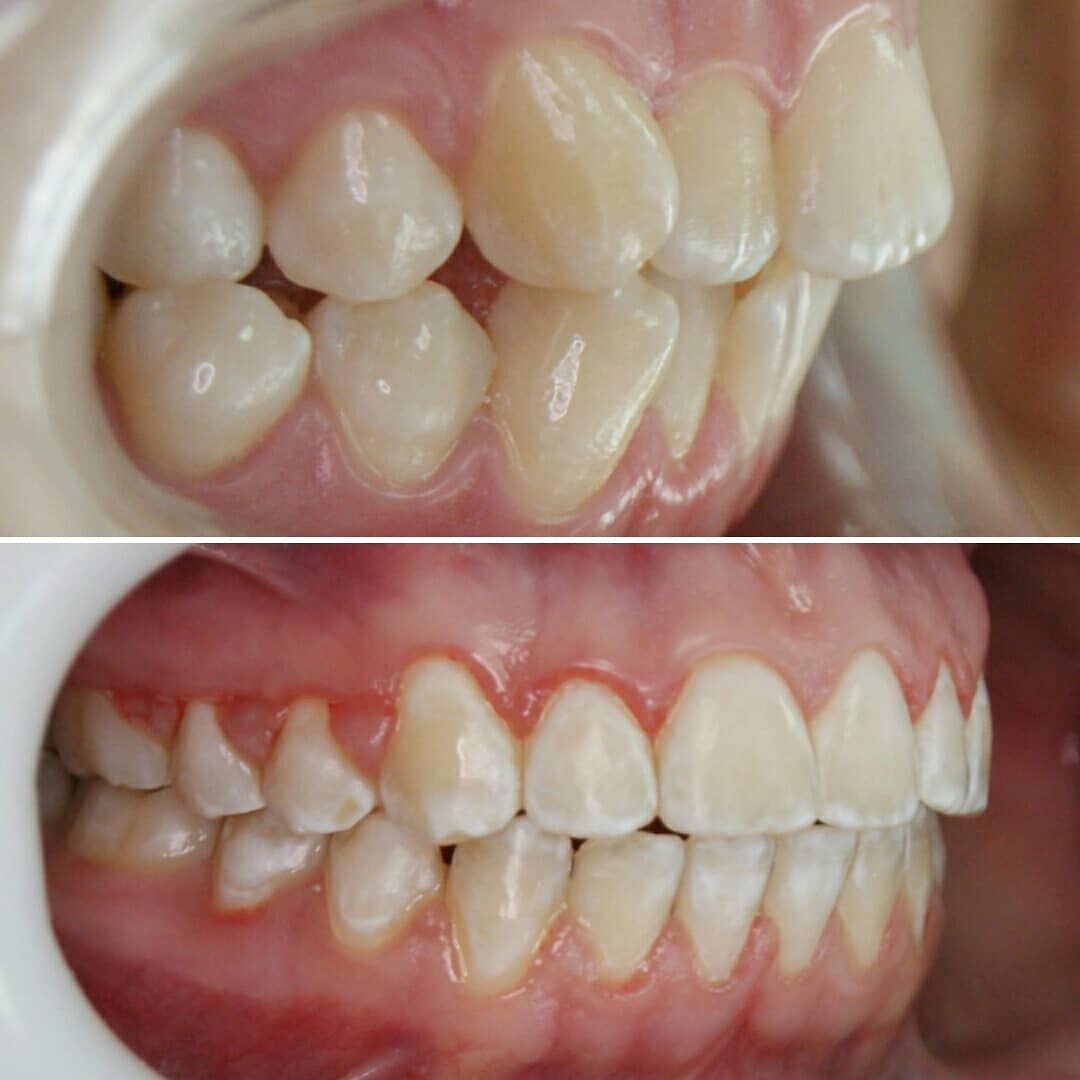

🔷️ Промежуточный результат лечения на аппарате Марко Роса (6 месяцев). Пациенту 7 лет. Самое удивительное - как "отвечает" на лечение нижняя челюсть: расширяется, меняется её положение и корректируется дистальный прикус, выравниваются нижние зубы, хотя никаких аппаратов на нижней челюсти не было!

P.S. Каждый случай уникальный, чаще нижнюю челюсть мы всё таки расширяем тоже.